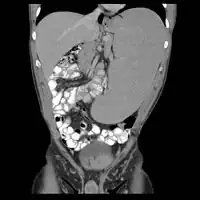

Non-Hodgkin lymphoma - splenic involvement